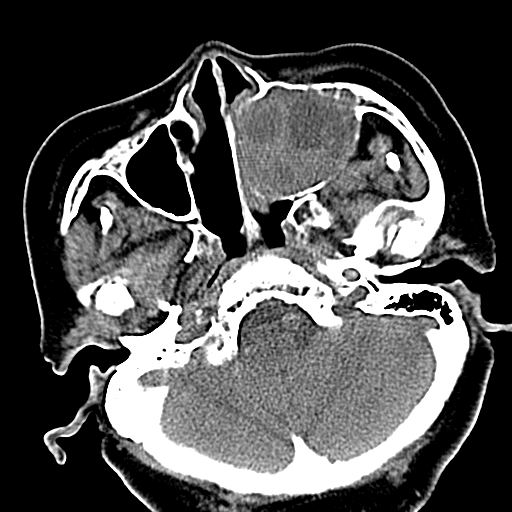

标题: CT19708:单侧上颌窦病变

老年患者,女。鼻塞多年。

考虑右侧上颌窦良性占位性病变,粘液囊肿可能性大;建议活检。

膨胀性生长,且骨质无破坏,说明时间久,良性;从密度,边缘看,内部还见坏死区,应该是实性肿瘤,定性,影像学无绝对的特异性

病灶密度很不均匀,骨壁膨胀中有断裂,考虑内翻乳头状瘤可能性大,粘液囊肿不排除

膨胀性生长,且骨质无破坏,说明时间久,良性;从密度,边缘看,内部还见坏死区,应该是实性肿瘤,定性,影像学无绝对的特异性,考虑内翻性乳头状瘤可能